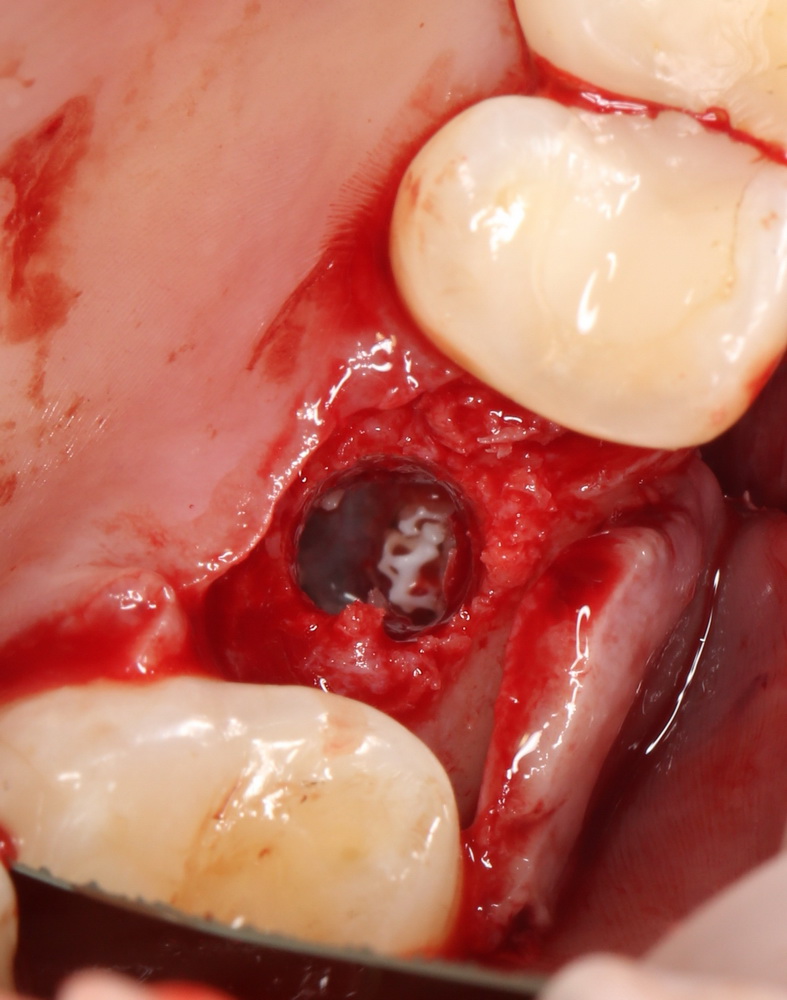

Синуслифтинг и удаление зуба

В некоторых случаях мы можем сочетать операцию синуслифтинга с удалением зуба. Это значительно сокращает сроки имплантологического лечения. Данная методика применяется при невозможности проведения немедленной имплантации одновременно с синуслифтингом.

Необходимым условием для проведения этого вмешательства является стадия ремиссии воспалительного процесса в области удаляемого зуба, отсутствие или небольшие размеры очагов хронического воспаления в прикорневой зоне (рис 49, 50, 51):

Рисунок 49, 50, 51. Проведение операции синуслифтинга одномоментно с удалением зуба: слева – скелетирование стенки верхней челюсти, подготовка к удалению зуба, в центре – лунка удаленного зуба (виден небольшой очаг деструкции костной ткани вследствие хронического периодонтита), справа – заполнение субантральной полости спейсером.